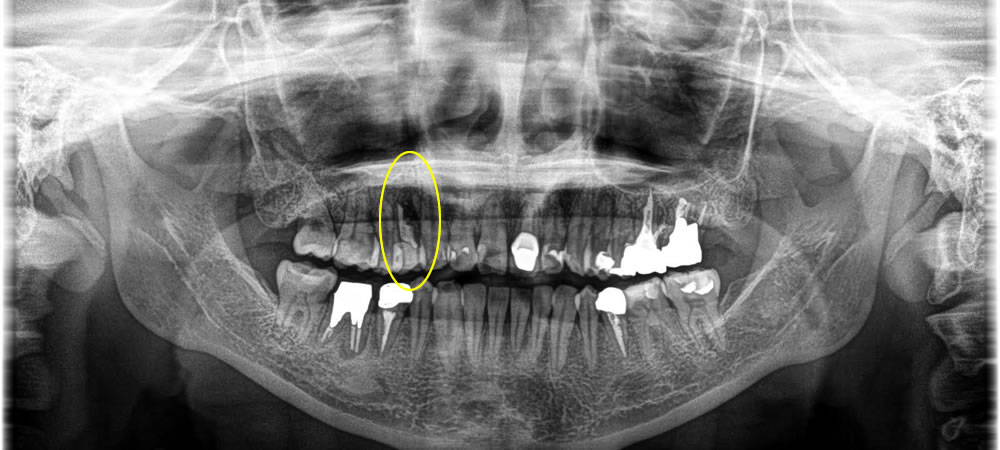

保存不可能な歯を抜歯即時インプラントで治療した症例

他院にて残すことができないと診断された歯にインプラント治療を行いたいとの事で来院された患者さまです。患者さまと相談し、抜歯即時インプラントで治療することになりました。

まず歯を抜いたところ、骨の横が感染により吸収されて大きく穴が空いてしまっていました。抜歯窩にインプラントを埋入し、骨を作る処置(骨造成)を行いました。